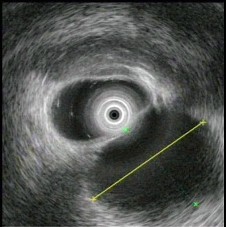

(单选题)超声内镜如图,B超引导穿刺检查示渗出液,淀粉酶265U/L。此患者的诊断()。

A:急性胰腺炎伴假性囊肿

B:慢性胰腺炎伴假性囊肿

C:胰腺囊腺癌